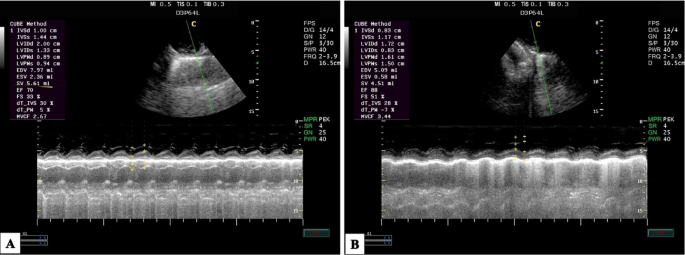

Furthermore, the following parameters were assessed: the mean arterial blood pressure (MAP), heart rate (HR), respiratory frequency (fR), oxygen saturation of hemoglobin (SpO2), end-tidal carbon dioxide concentration (EtCO2), and rectal temperature (RT) were measured at previous time points using a multi-parameter monitor (Aisys Carestation, General Electric Co; Datex-Ohmeda, GE Healthcare Inc., Madison, WI, USA). Additionally, the echocardiographic examination was conducted using portable ultrasonographic equipment (Esaote MylabTM 30 Vet Gold, Brazil) with a sectoral transducer (PA240) at a frequency range of 1 to 4 MHz. These parameters were assessed at different time points: before the administration of pre-anesthetic medications considered as a baseline (M0); 30 min after the administration of pre-anesthetic medications (M1); immediately after intubation (M2); and at 10, 20, 30, 40, and 50 min after maintaining anesthesia (T10, T20, T30, T40, and T50).

The dogs were placed in right lateral recumbent positions, and echocardiographic measurements followed the guidelines outlined in the literature40,41,42,43,44,45. In the right parasternal window, on the transverse axis, the following parameters were evaluated using M mode: diastolic and systolic interventricular septum thickness (IVSd and IVSs cm), diastolic and systolic left ventricular internal diameter (LVIDd and LVIDs cm), left ventricular posterior wall thickness at end-diastole and end-systole (LVPWd and LVPWs cm), interventricular septal thickness at end-diastole and end-systole (IVSTd and IVSTs cm), left ventricular volume at end-diastole and end-systole (EDV and ESV ml). The stroke volume (SV ml), fractional shortening percentage (FS%), ejection fraction percentage (EF%), and the left atrial/aortic diameter ratio (La/Ao ratio) were calculated from the measurements performed in M mode.

The effects of acepromazine/methadone, ketofol, and atracurium/ketofol during the experimental period on the echocardiographic parameters between the groups and within the same group are presented (Table 2). Echocardiography findings of SV, EF%, and FS% were significantly affected by the time for ketofol (P = 0.012) and atracurium/ketofol (P = 0.031) compared with the post-sedation period M1. However, the AKFG recorded significantly higher values (P ≤ 0.05) of SV, EF%, and FS% at M2 compared with the KFG during the maintenance period of anesthesia.

Consistent with38, left ventricular end-diastolic diameter (LVDd) and left ventricular end-systolic diameter (LVDs), as well as the other parameters, were significantly decreased after sedation with acepromazine/methadone compared to the baseline values. The decrease in LVDd and LVDs can be attributed to the hypotensive effects induced by the combination of acepromazine and methadone. Moreover, this reduction in diameter is sufficient to result in a decrease in the left ventricular volume and aortic diameters. When comparing the KFG to those in the baseline measurements, statistically significantly lower EF% and FS% were reported. The hypotensive effects of acepromazine, methadone, and propofol administration may be the cause. In the case of reduced blood flow to the heart, the passive pathway of blood from the left atrium to the left ventricle remains relatively constant, which may result in a smaller blood volume available for the active pathway. Therefore, it may lead to an increase in these parameters41.

The cardiac parameters, such as FS%, EF%, and SV, exhibited significant changes until the end of the anaesthetic period (P ≤ 0.05) in dogs that received the AKFG compared to the KFG. The most significant difference between the M1 and T10 was observed when atracurium and ketamine were administered via bolus injection. Interestingly, the wall thickness did not rapidly increase, suggesting that ventricular myocardial fibers in postnatal dogs tend to elongate more than they widen. Another possibility is that myocardial density increases with age while extracellular water concentration decreases. In addition, age had a significant impact on the mean values of left ventricular posterior wall thickness (LVPWs) and interventricular septal thickness at end-diastole (IVSd)74.